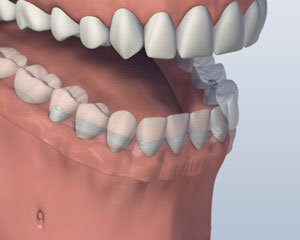

Another option involves placing four to six implants, depending on your jaw size or shape, into your lower jaw. After healing is complete, the implants are connected with a custom-made support bar. Your denture will be made with special internal retention clips that attach onto the support bar, enabling the denture to snap firmly into place. This is called an “overdenture.” The advantage of this option is that it is much more stable than the first option and allows very little denture movement. Your denture is still removable for easy cleaning and maintenance.

1. Before

2. Implants Placed

3. Denture Attached